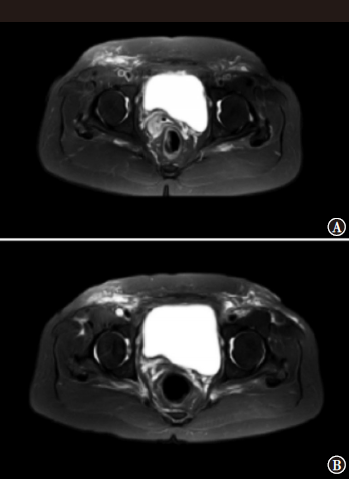

盐酸安罗替尼为多靶点小分子酪氨酸激酶抑制剂,可作用于肿瘤新生血管,并诱导肿瘤细胞凋亡,其广泛应用于肾细胞癌、结直肠癌、肝癌等肿瘤的治疗。本例应用放化疗联合盐酸安罗替尼治疗复发性子宫内膜癌患者,取得满意的疗效。